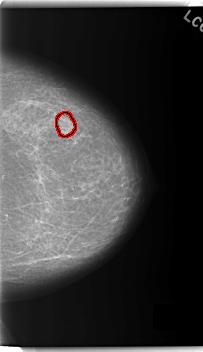

C_0160_1.LEFT_MLO

LEFT_MLO LINES 5888 PIXELS_PER_LINE 3504 BITS_PER_PIXEL 12 RESOLUTION 50 OVERLAY

FILE: C_0160_1.LEFT_MLO.OVERLAY

TOTAL_ABNORMALITIES 1

ABNORMALITY 1

LESION_TYPE MASS SHAPE LOBULATED MARGINS ILL_DEFINED

ASSESSMENT 4

SUBTLETY 4

PATHOLOGY MALIGNANT

TOTAL_OUTLINES 1

BOUNDARY